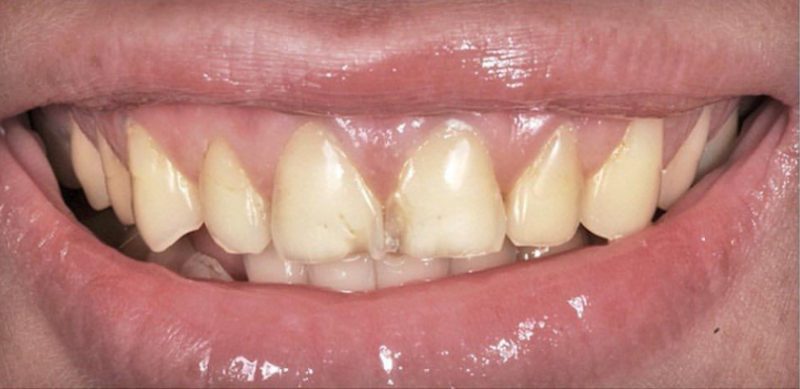

TREATMENT: VENEERS & CROWNS

Patient: Melanie

Before coming to Riverside Tooth Co., Melanie was fearful of the dentist and apprehensive about getting cosmetic work. After visiting our office, our compassionate, skillful team worked with Melanie to develop a treatment plan that fit her needs and far exceeded her expectations. In under two weeks, Dr. Sandhu transformed Melanie’s cracked, discolored teeth and restored her smile.